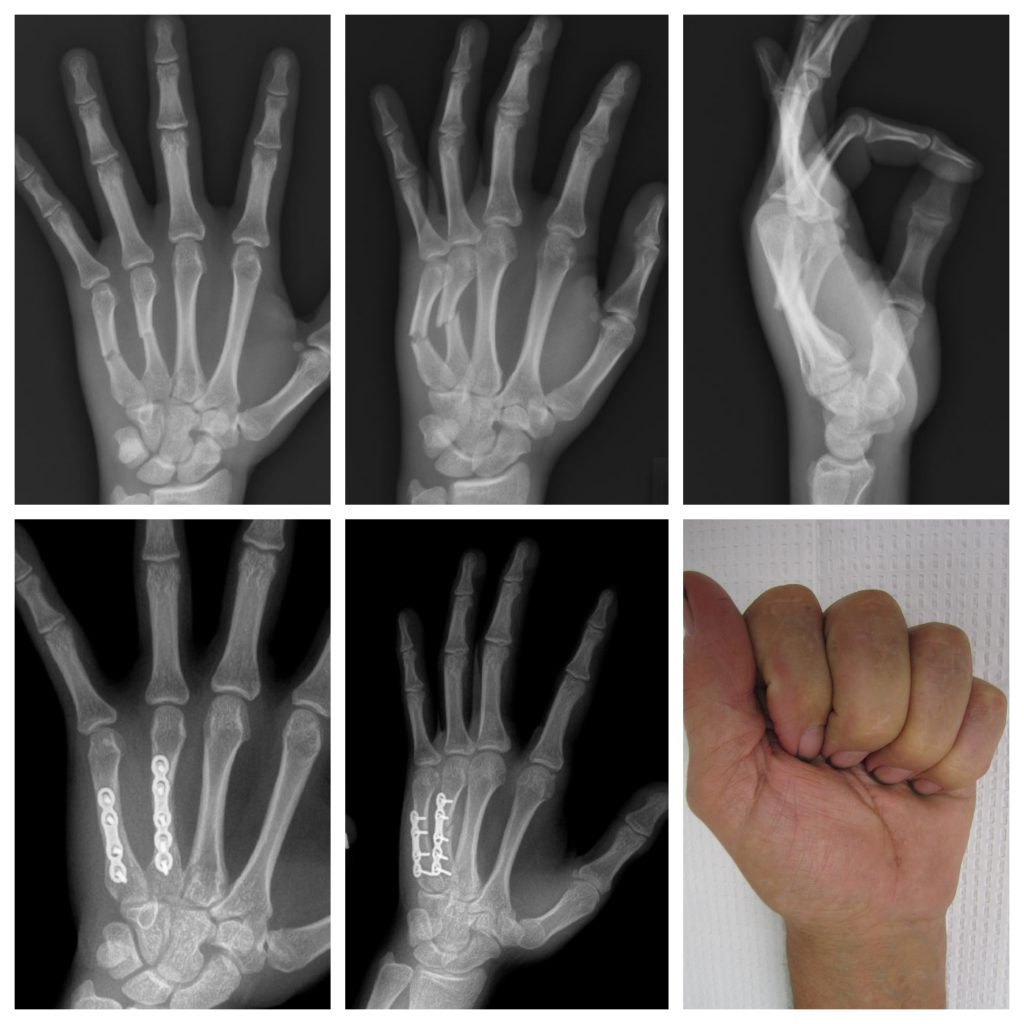

ORIF of multiple metacarpal fractures

Images below are from a patient with 4th and 5th metacarpal shaft fractures in the hand. The fractures were displaced and unstable, requiring surgery to improve the patient’s hand function. ORIF with plates and screws was performed and a good result was achieved for the patient.